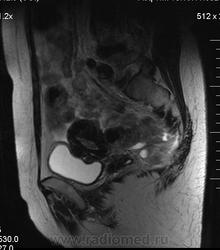

в-целом, cогласен. Карциноматоз тоже есть. Видится еще диффузный аденомиоз матки (задней стенки).

Мне кажется, что есть инфильтрация и передней стенки прямой кишки.